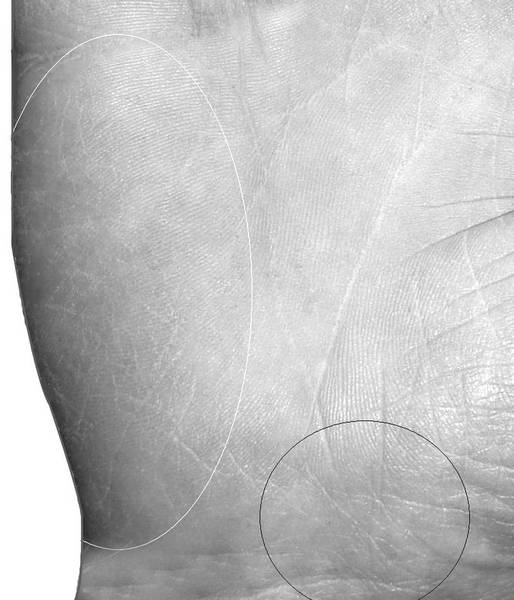

Рак пищевода отображается длинной извилистой линией, исходящей из большого треугольника на холм Луны, доходящей до расцетт и оканчивающейся разветвлением, либо прямоугольником, расположенным на линии Сердца под холмами Сатурна и Аполлона. На рисунке 1.98 представлена рука мужчины с раком пищевода 4 стадии, где обозначены знаки, дающие в комплексе указание на онкологию: в белом круге выделен знак острова в нижней трети линии Жизни, а в черном овале прямоугольник, расположенный на линии Сердца под холмами Сатурна и Аполлона.

Рис. 1.98